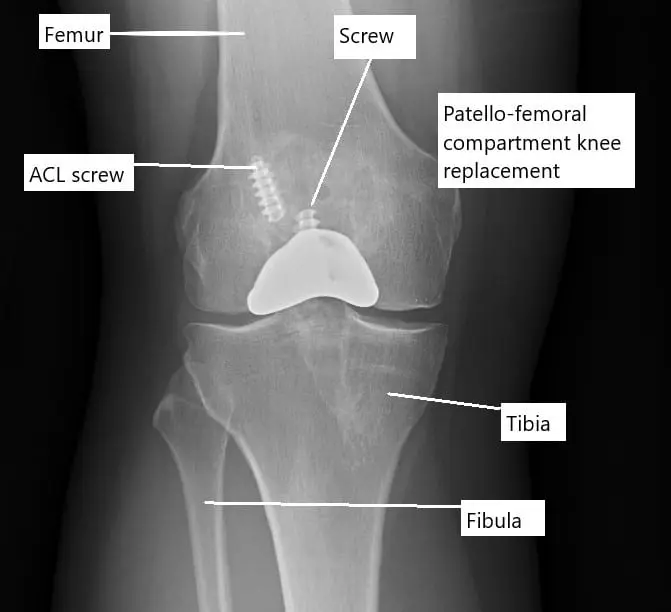

X-ray showing a partial knee replacement.

Partial knee replacement replaces only one worn compartment. The surgeon uses a smaller incision and removes only the damaged bone surfaces. Ligaments and other soft tissues remain intact. This allows more natural knee motion and quicker recovery.

Partial knee replacement

In a partial knee replacement, only one of the compartments of the knee is replaced. During a partial knee replacement surgery, the surgeon accesses the joint through a usually smaller incision. The diseased ends of the bones forming the compartment are then cut to be removed. All the ligaments and other soft tissue structures are left intact.

A metal prosthetic component is placed on the cut bony ends and fixed with bone cement. A high-grade plastic part is placed in between the metal parts for the smooth gliding of the metal surfaces. The incision is closed in layers and the patient is able to walk the same day of the surgery.